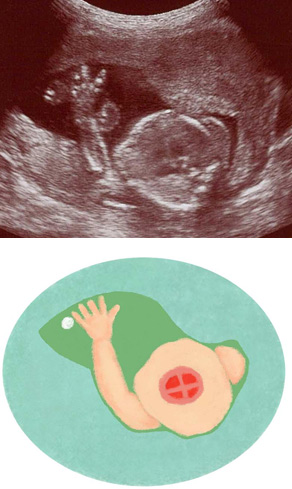

妊娠21週ころの超音波写真

胴体の断面から心臓を見た際に、赤ちゃんの手が動いて写り込んだもの。心臓は4つの部屋に分かれています。心臓など臓器が成熟し、また、手足の動きは滑らかになってきます。